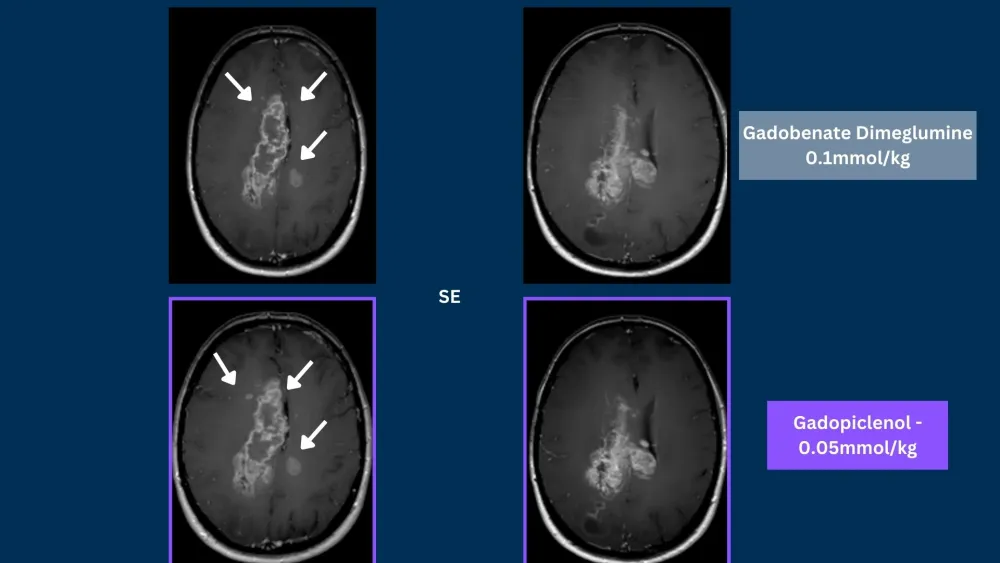

Phase III clinical trials, in CNS and Body, demonstrated that gadopiclenol at a dose of 0.05 mmol/kg was noninferior to gadobutrol at a dose of 0.1 mmol/kg in terms of lesion visualization.5,6

SE = Spin Echo, GRE = Gradient Echo, 3DGRE = 3D Gradient Echo, TSE = Turbo Spin Echo

Phase III PROMISE trial in the body demonstrated that gadopiclenol at a dose of 0.05 mmol/kg was noninferior to gadobutrol at a dose of 0.1 mmol/kg in terms of lesion visualization.6

Phase III PICTURE trial in CNS demonstrated that gadopiclenol at a dose of 0.05 mmol/kg was noninferior to gadobutrol at a dose of 0.1 mmol/kg in terms of lesion visualization.5